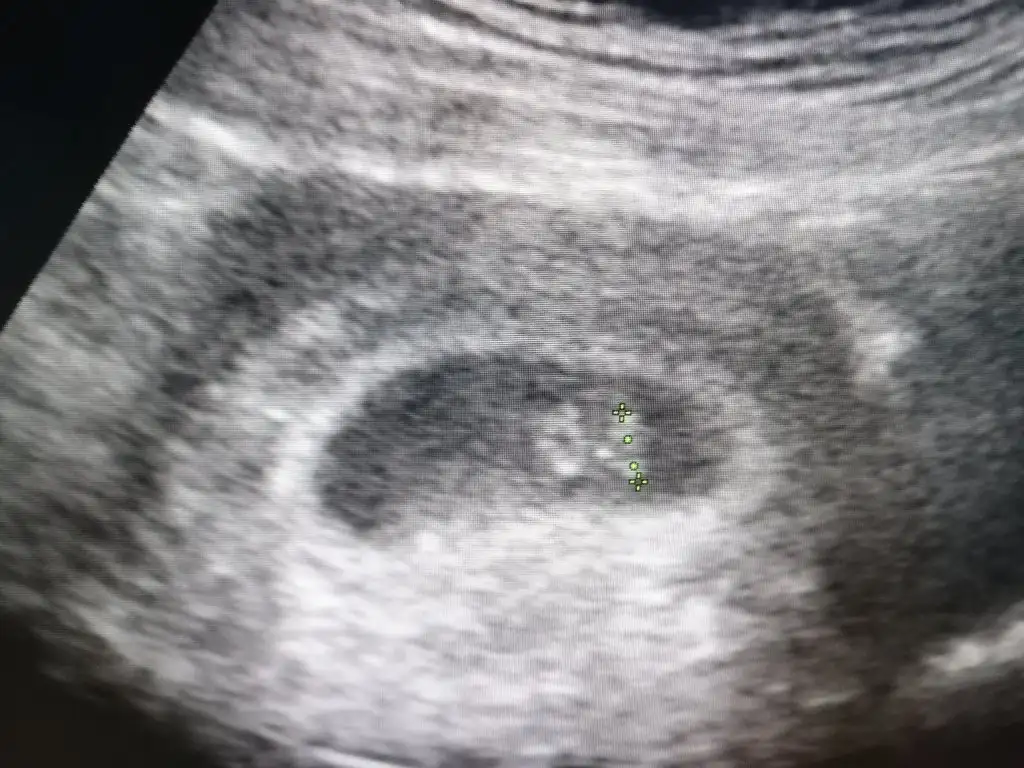

Benimde yarin canim insallah bizde duyariz kalp atisiniGünaydın kızlar bende acayıp açlık hıssıyle uyandım bugun iş yerıne zor attım kendımı :) yarın doktor randevum var kalp atısı ıcın cok heyecanlıyım![]()